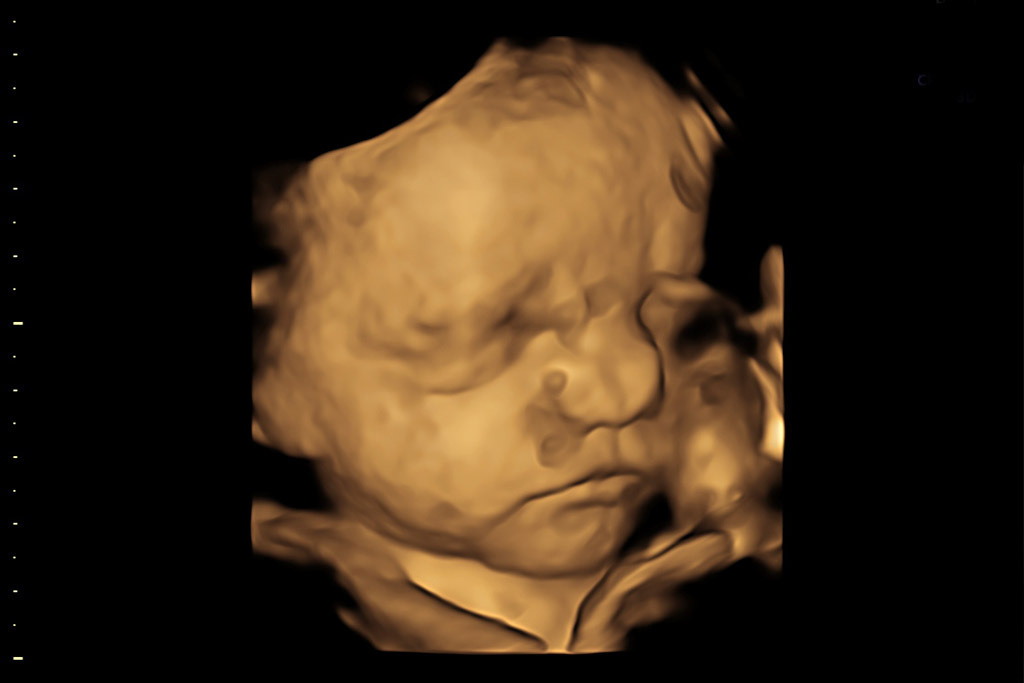

Ecografía 5D

La Ecografía en 5D HDLIVE permite la obtención de imágenes y vídeos del bebé en tiempo real con una calidad máxima, superior a la ecografía 4D, con textura y colores muy similares a los reales. En Clínica del Río-Hortega disponemos de un equipo de última generación con un ecógrafo que permite obtener imágenes 5D HDLive con el que poder captar los momentos previos al parto de la forma más real que existe en la actualidad.